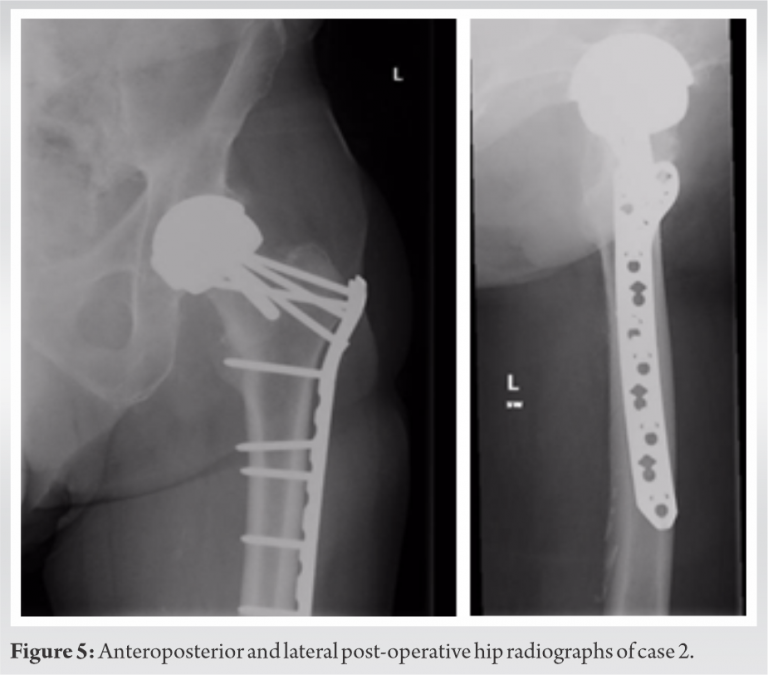

The three cases that we describe in this paper are homogenous in presentation, treatment and outcome, and therefore presented in the table below (Table 2). Pre-operative (Fig. 1-3) and post-operative (Fig. 4-6) radiographs are also included for each of the cases. 3-D reconstructed images from a computerized tomography (CT) scan for case 3 can be visualized as part of (Fig. 3).

All patients were independently mobile, active with well-fixed and well-functioning RHAs before the date of injury. All patients suffered low-energy trauma causing the fracture. All patients underwent CT scans to further delineate the fracture pattern, to assess for radiographic signs of loosening, and to assess bone stock and suitability for fixation. Intraoperatively, patients were placed on a traction table. Optimal closed reduction of the fracture was achieved using intraoperative image intensifier (II). An extended direct lateral approach to the proximal femur was used. The fascia lata was divided along its fibers and the vastus lateralis split. Fracture reduction was improved, held with 2 mm Kirschner wires placed across the fracture site, and position confirmed with II. An anatomically contoured distal femoral variable angle LCP (VA-LCP) intended for the contralateral distal femur was measured, selected, and positioned in an inverted manner (proximal and distal ends reversed). The position was checked using image intensifier. A non-locking fully threaded cortical screw was inserted distal to the fracture site to seat the plate to bone. The senior author believes that it is essential to achieve the best possible screw hold in the neck, and therefore accept to some extent that the plate distally may not sit perfectly centered over the shaft of the femur. Shaft screws can be inserted distally through a minimally invasive plate osteosynthesis technique if desired. All patients were asked to partially bear weight on the operated side for 8 weeks. The time to radiographic union and the time to discharge from physiotherapy with achievement of previous level of function were recorded for two patients. One patient, case 3 (Fig. 3, 6), was lost to follow-up as she moved out of the country.

The literature suggests two distinct fracture modalities emerging in the presence of an RHA: “Atraumatic” and “traumatic.” The predominant mode is an insidious “atraumatic” type of injury that is more often intracapsular and frequently undisplaced or minimally displaced at presentation. According to Carrothers et al., this was the most common cause of revision in a review of 5000 resurfacings [4]. Although there have been reported cases of implant retention in these types of injuries [8, 9], revision arthroplasty is the recommended definitive treatment [2]. The “traumatic” modality occurs in the setting of trauma and therefore does not have a defined timescale or incidence. This subset of fractures is predominantly extracapsular in nature [15, 20], although sub-capital fractures can occur [18]. Favorable results have been reported for extramedullary fixation of intracapsular fractures within this “traumatic” group [34], although once again the recommended course of action is revision arthroplasty. Complex arthroplasty treatment decisions are best made in conjunction with multidisciplinary team (MDT) discussions, as these cases were [35]. This paper presents 3 cases of fracture around well-fixed and well-functioning hip resurfacing arthroplasties in independent high functioning individuals. To reduce the risks associated with revision arthroplasty and following discussions with the MDT as well as the patients, fixation was the selected treatment in these cases. A distal femoral VA-LCP condylar plate was used as it has more screw options compared to most proximal femoral locking plates. The reversed distal femur plate of the contralateral limb has an anatomic profile that sits well in the proximal femur and allows for increased screw purchase and screw density in the proximal femur around a RHA. It was also decided to avoid using plates with greater trochanteric extensions to reduce the risk of lateral hip pain, iliotibial band irritation, and need for future removal of metalwork. Patients are suitable for this treatment if they have a well-function and well-fixed prosthesis, if they have good bone stock and are able to fully or partially bear weight without discomfort (in the opinion of the operating surgeon and MDT). An inability to bear weight, in these cases, could be viewed as a surrogate marker of fitness and further guide the decision to fix or revise. Revision to a total hip replacement remains the treatment of choice for a failed resurfacing, where the mode of failure is loosening, osteonecrosis of the head and collapse, or early fracture due to poor positioning or patient factors. Several studies have shown that the outcome from revision does significantly reduce patient-reported outcome measures (PROMS), when compared to pre-revision or even pre-primary surgery level [29, 36]. Whilst it is recognized that conservative management is an option, particularly in the undisplaced and potentially incomplete fracture, the risks associated with non-operative management of patients with neck of femur fractures are not acceptable to the active and high functioning patient. These risks include fracture displacement, non- and mal-union, and reduced mobility [8, 9, 31]. Complications of fixation around the femoral prosthesis of a hip resurfacing arthroplasty include increased risk of deep vein thrombus or pulmonary embolus due to non-weight-bearing status and increased immobility in the rehabilitation period. In addition, trochanteric bursitis and plate irritation may necessitate the removal of the plate. Other complications include periprosthetic fracture distal to the plate fixation, non- and mal-union, and a potentially more complex revision surgery to THA in the future (if required). Avascular necrosis and subsequent collapse if blood supply to the femoral neck is disrupted are a possibility, but this is more likely in the case of an intracapsular fracture, as reported in one case study [18]. The current literature regarding the treatment of pertrochanteric fractures around a well-fixed and well-functioning hip resurfacing almost universally reports favorable outcomes following fixation with both proximal and distal locking compression plating or intramedullary nailing and there is a substantial body of evidence built up over several years that include 11 cases so far with an outcome of radiological union [12, 15, 17, 21, 22, 23, 25, 26, 29]. In summary, we present our technique that is reproducible and achieves good fixation into the femoral neck. This is yet another tool in the surgeons’ armamentarium of techniques to treat these difficult fractures.